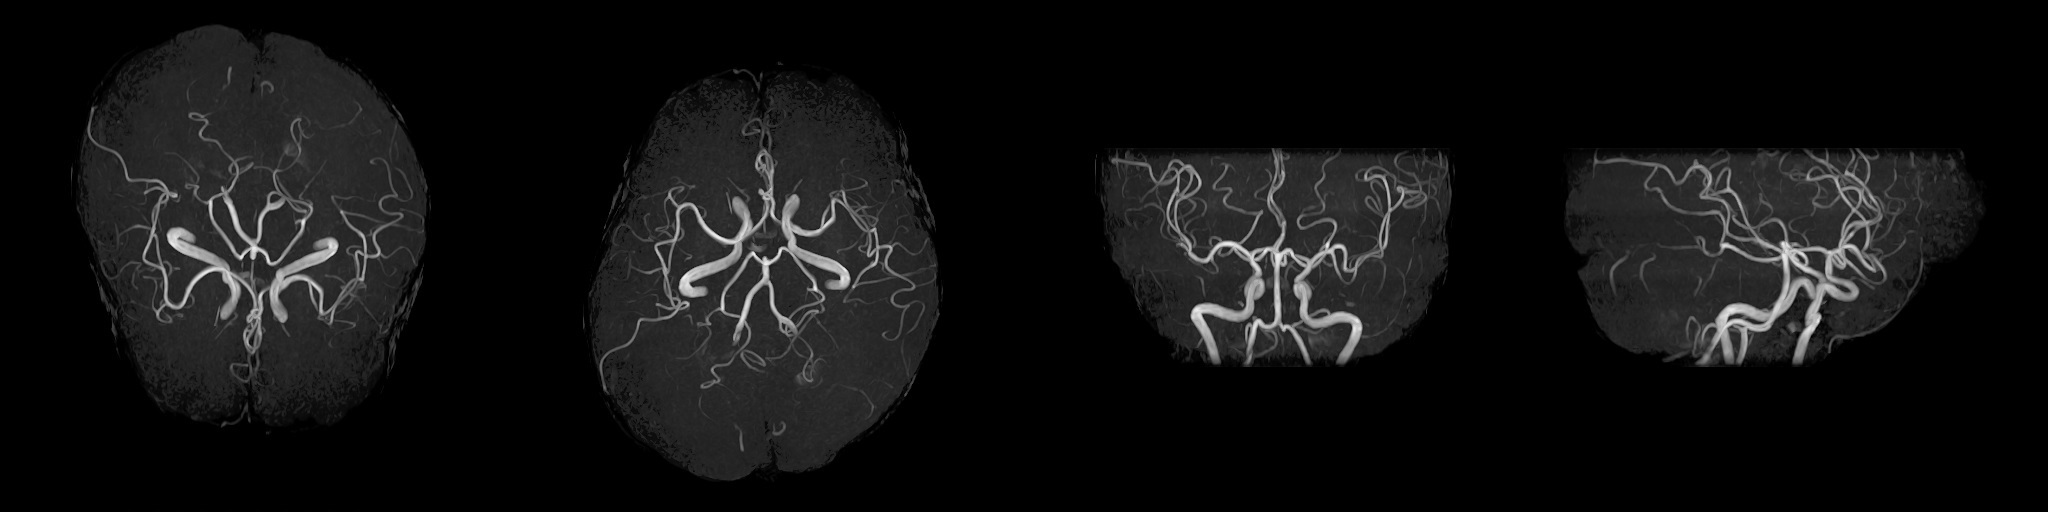

MRI(磁気共鳴画像)装置

2022年2月にMRI装置を更新いたしました。

1.5TのMIR装置(富士フイルムヘルスケア株式会社製「MRイメージング装置 ECHELON Smart」)を導入し、以前よりも短い時間で高画質の撮像が可能になりました。

MRIは体内の断面像を縦、横、ナナメから人体に悪影響を与えずに見ることが出来る装置です。わずかな病変も見逃さない鮮明な画像は腫瘍などの早期発見や健診に威力を発揮します。薬品を全く用いずに血管撮影等が出来るので、患者さんは動かずに横になるだけで苦 痛なく精密検査が受けられます。

MRA

頭部